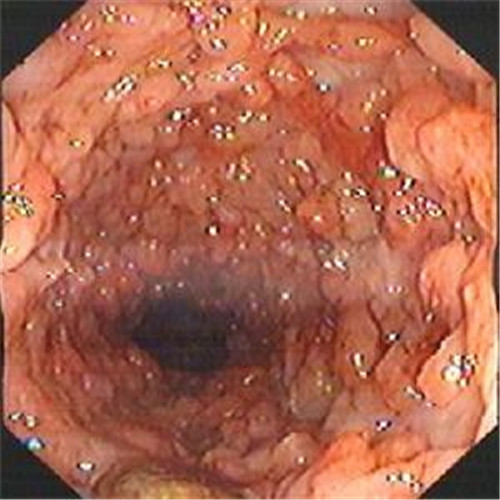

潰瘍性結腸炎水腫